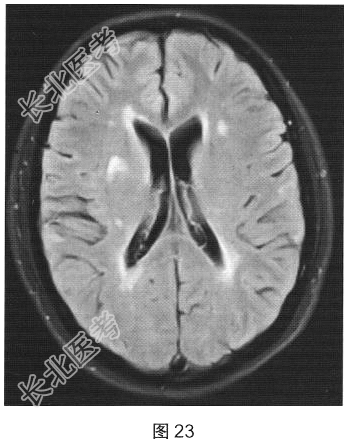

- 简答题2、[提示]患者行脊柱MRI平扫及增强检查,如图25、图26所示。关于MRI检查结果,请描述一下。

- 简答题3、根据脊髓和颅脑MRI表现,病变应诊断为?